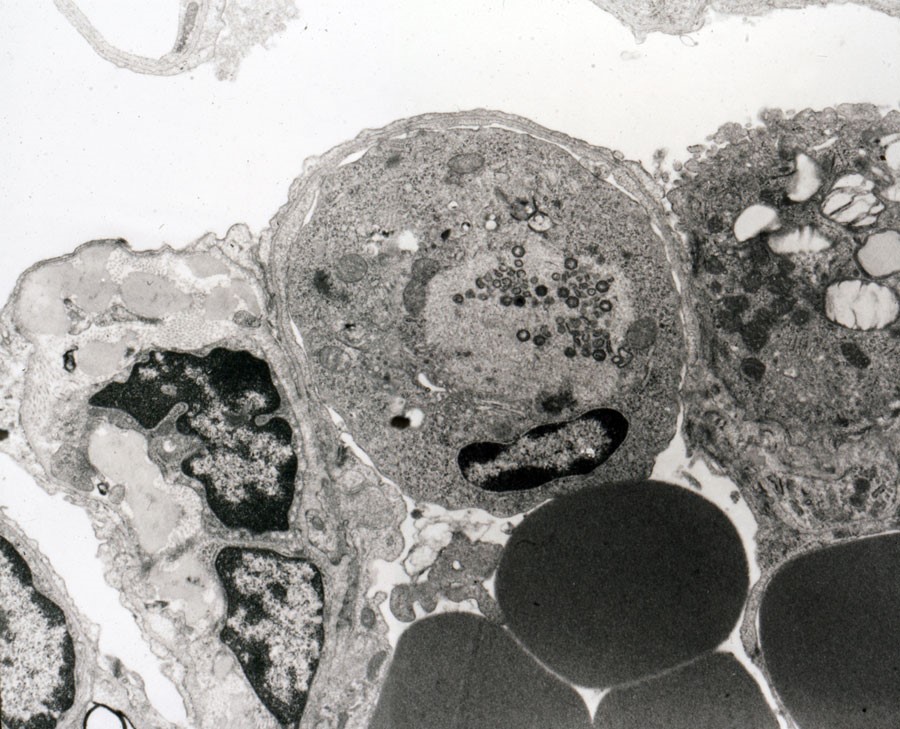

Вирус африканской болезни лошадей - фото презентация